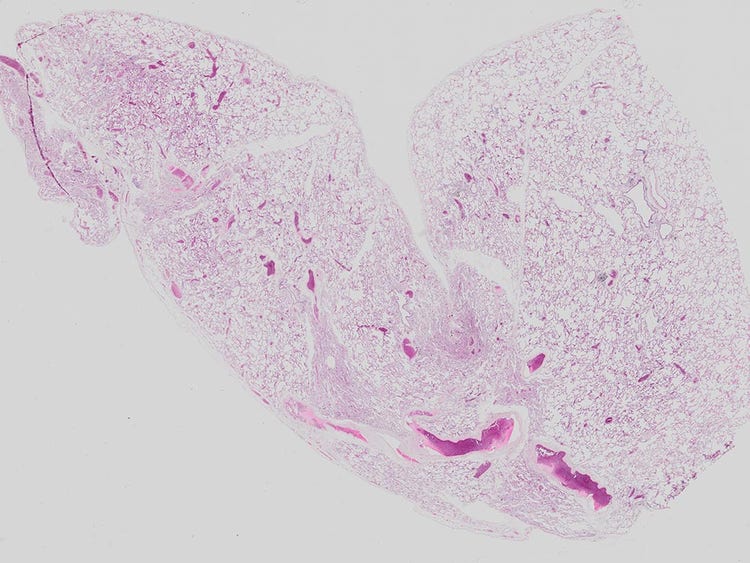

• Faites l’acquisition d’images d’échantillons de tissus entiers ou évaluez rapidement l’état des flacons de culture cellulaire sur de grandes zones en haute résolution.

• L’assemblage de haute précision rend presque invisibles les jonctions entre les images dans les modes d’acquisition en fond clair et de fluorescence.

• Même les échantillons inclinés ou irréguliers peuvent être assemblés de manière impeccable.

Image de poumon de souris prise avec un objectif UPLXAPO4X. Coloration : HE.